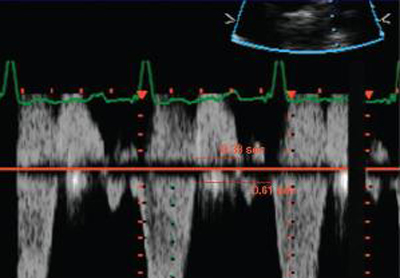

Doppler in a patient with pulmonary regurgitation following repair of tetralogy of Fallot. The patient has a restrictive right ventricle, and Doppler shows evidence of restriction with an antegrade ‘A’ wave in the pulmonary artery

From: Chaturvedi RR, Redington AN. Heart. 2007 Jul;93(7):880-9; used with permission